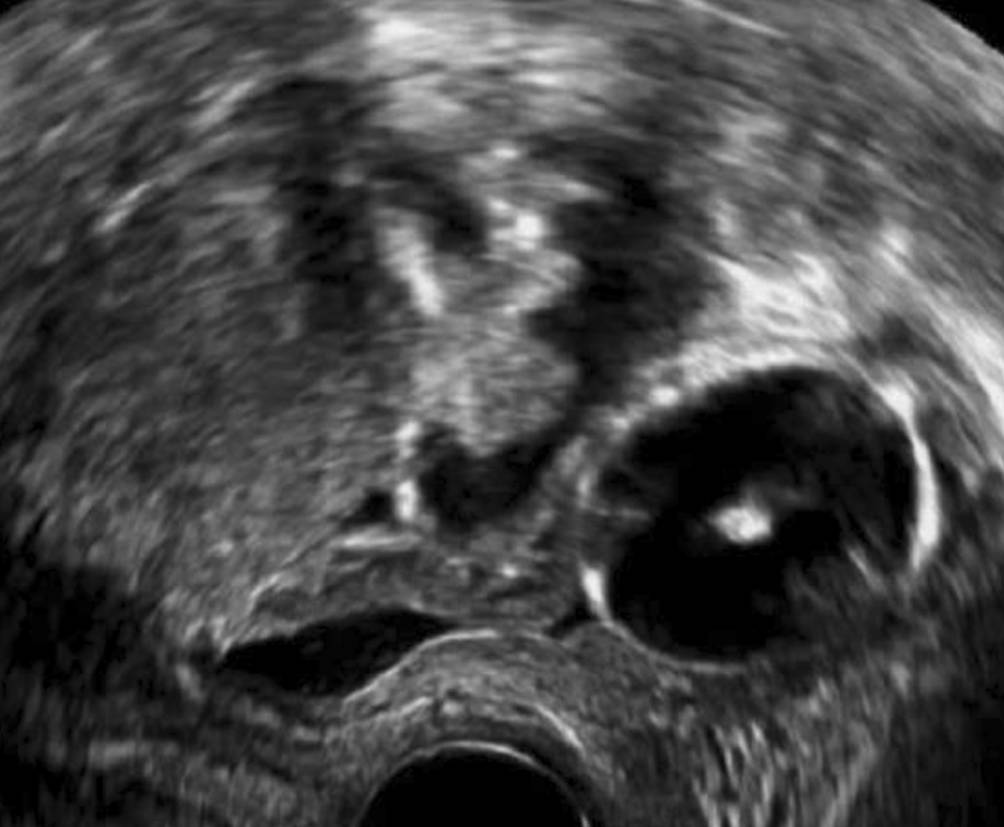

Beckenniere

Beckennieren sind bei Frauen wesentlich häufiger als bei Männern und häufiger auf der linken als auf der rechten Seite. Meist sind sie den Patientinnen bekannt, sie können aber durchaus auch bei einem Vaginalultraschall erstmals auffallen. Da die Rotation der Nieren im Zuge der embryonalen Entwicklung einer Nierendystopie auch gestört ist, liegt das Nierenbecken ventral des Nierenparenchyms und nicht medial. Die Beckenniere sieht also nicht aus wie eine „typische“ Niere im Ultraschall und kann auf den ersten Blick auch für einen soliden Ovarialtumor gehalten werden (Abb. 4). Steht die Diagnose fest, sollte die Gelegenheit genutzt werden, gleich mit 3‑D-Ultraschall nach Uterusfehlbildungen zu fahnden, da diese bei Nierendystopien gehäuft auftreten [1].

Abb. 4

Hier liegt die Beckenniere zwischen Zervix (unten) und Harnblase (rechts im Bild)